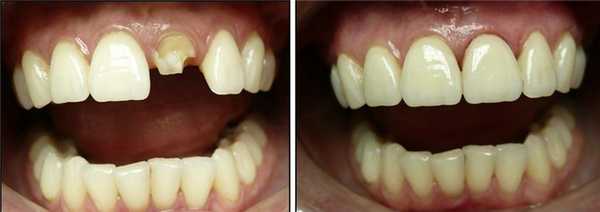

В данном клиническом случае я покажу как можно эффективно и точно провести метод инверсионного (обратного) протезирования.

Клинический случай

Пациентка М., 35 лет, обратилась в клинику с жалобами на расцементировку коронки из оксида алюминия на 2.1. Объективно: коронка имела подвижное положение на культе зуба 2.1 и без усилий извлеклась. Отмечался откол 1/3 культи зуба (внутренняя часть коронки была заполнена отделившимся фрагментом).

Выводы

Отдаленные клинические наблюдения показывают надежность и точность метода инверсионного протезирования. Данная методика может с успехом применяться в сложившихся клинических ситуациях.